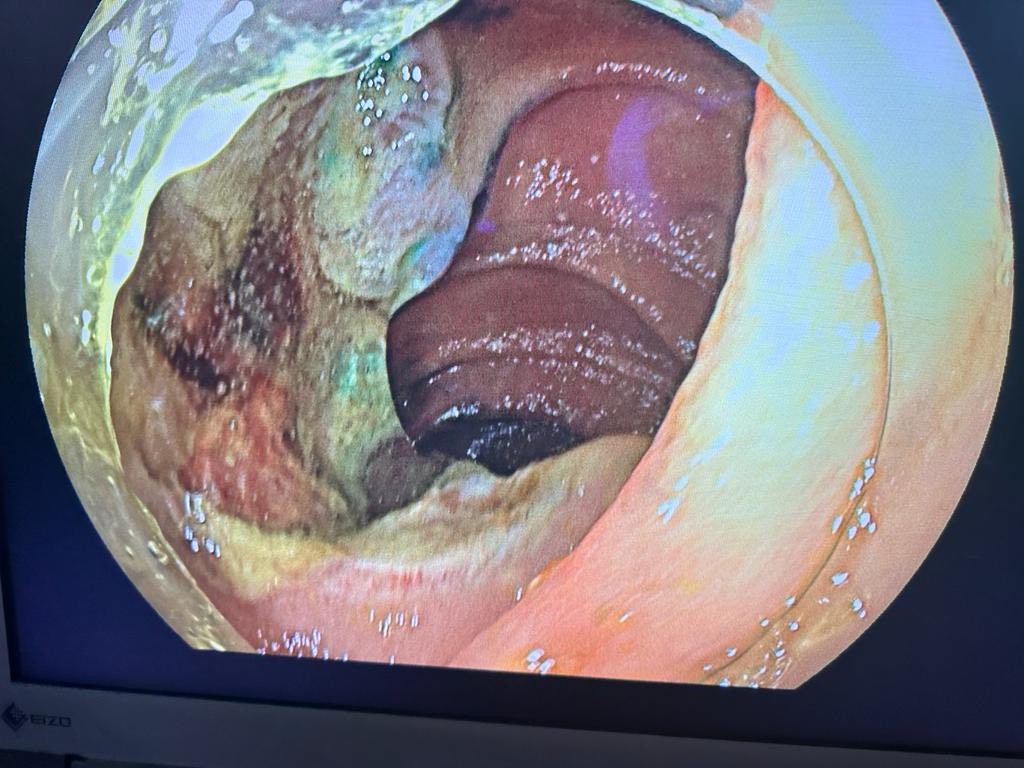

Just putting it here, 70 years old with 10 cm BE with HGD and sibling past away from esophageal cancer. ESD with 4 tunnels and complete resection of the lesion #endoscopy Bobby Jacob, MD Moamen Gabr